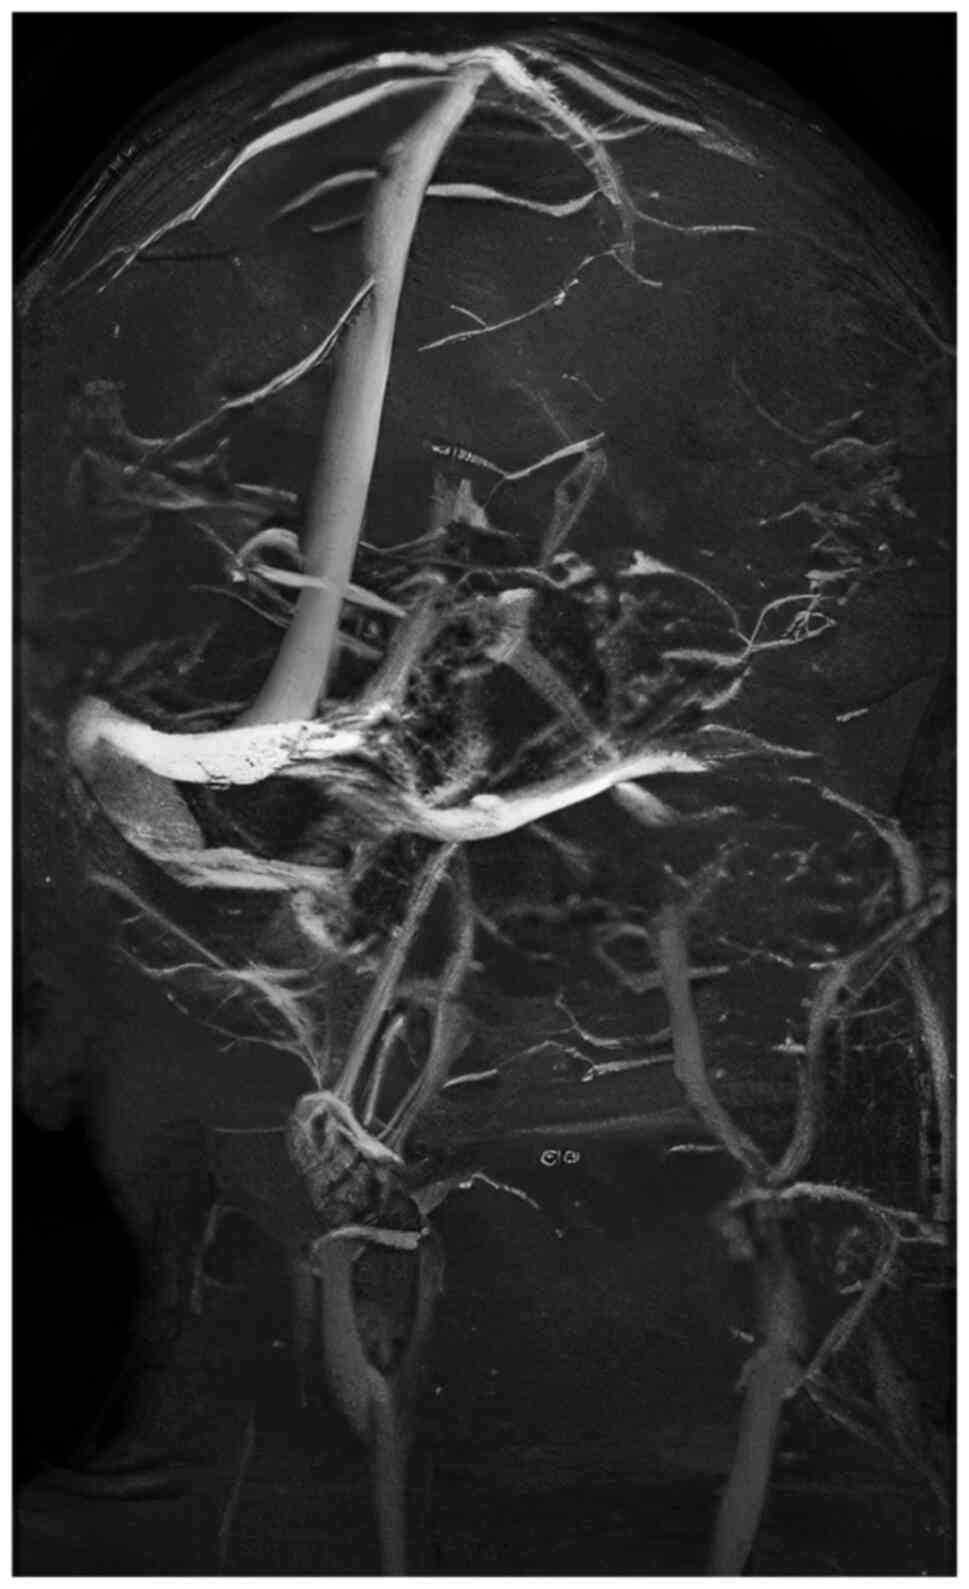

Magnetic resonance imaging showing left lateral sinus thrombosis involving the auditory meatus and acoustic nerve.

The computed tomography (CT) angiography highlighted lateral sinus thrombosis, affecting the internal auditory meatus and nerve.